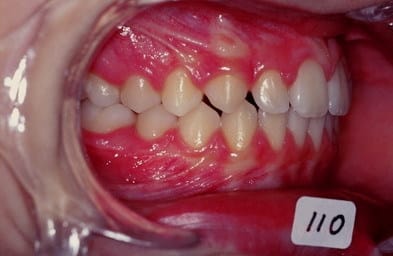

cas n 2

classe II 1 avec pouce